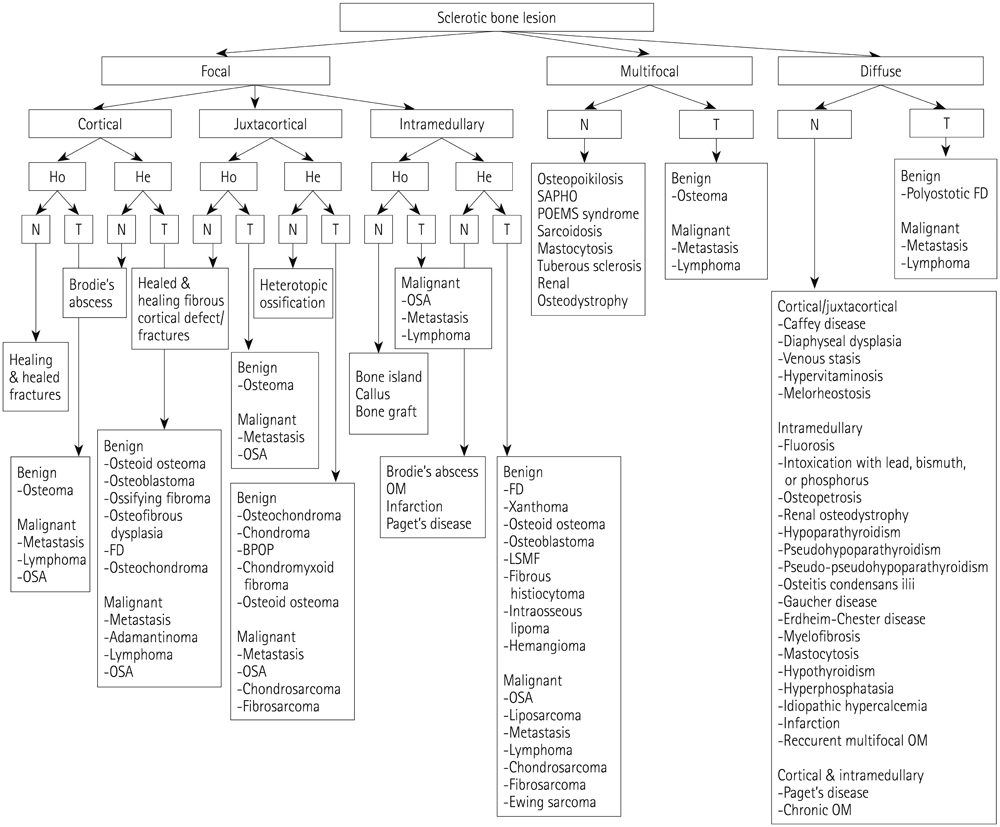

Systematic Approach of Sclerotic Bone Lesions Basis on Imaging Findings

- Sclerotic bone lesions are common, but there are diverse groups of tumors and non-tumorous lesions. Although plain radiograph and computed tomography can reveal important characteristics of these lesions, diagnosis is often challenging for radiologists. A systematic approach and familiarity with the imaging features of various sclerotic bone lesions may be greatly helpful for eliminating in the differential diagnosis. This review describes the systematic approach to diagnosing sclerotic bone lesions based on imaging findings.

Figure